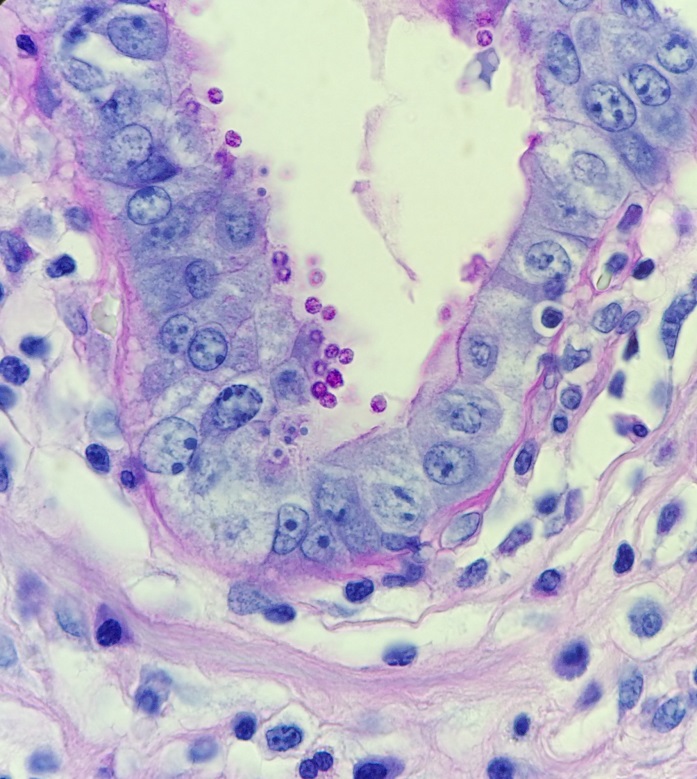

While the overall morphology was most consistent with Malbranchea species, rare slightly swollen arthrocondia were identified prompting increased handling precautions and further investigation into the patient’s clinical course at the referring hospital. After several more days of growth, a repeat cellophane tape test (Figure 3) demonstrated thick-walled, barrel-shaped arthrocondia alternating with empty cells as is characteristic of Coccidioides species.

In tissues and body fluids, Coccidioides is identified as round, thick-walled spherules (10-80µm) containing multiple endospores (2-5µm). When cultured at both 25°C and 37°C, Coccidioides forms wooly, white-grey colonies which may turn brown as they mature. The coarse hyphae are hyaline and septate with alternating thick-walled, barrel-shaped arthroconidia and empty cells. Although colonies usually form within three to five days, the distinctive arthroconidia may take up to 2 weeks to fully mature. Due to this delayed maturation, Coccidioides is often initially misidentified as its non-pathogenic look-a-like Malbranchea. Confirmatory testing by PCR may be performed on both bodily fluids and paraffin embedded tissue.